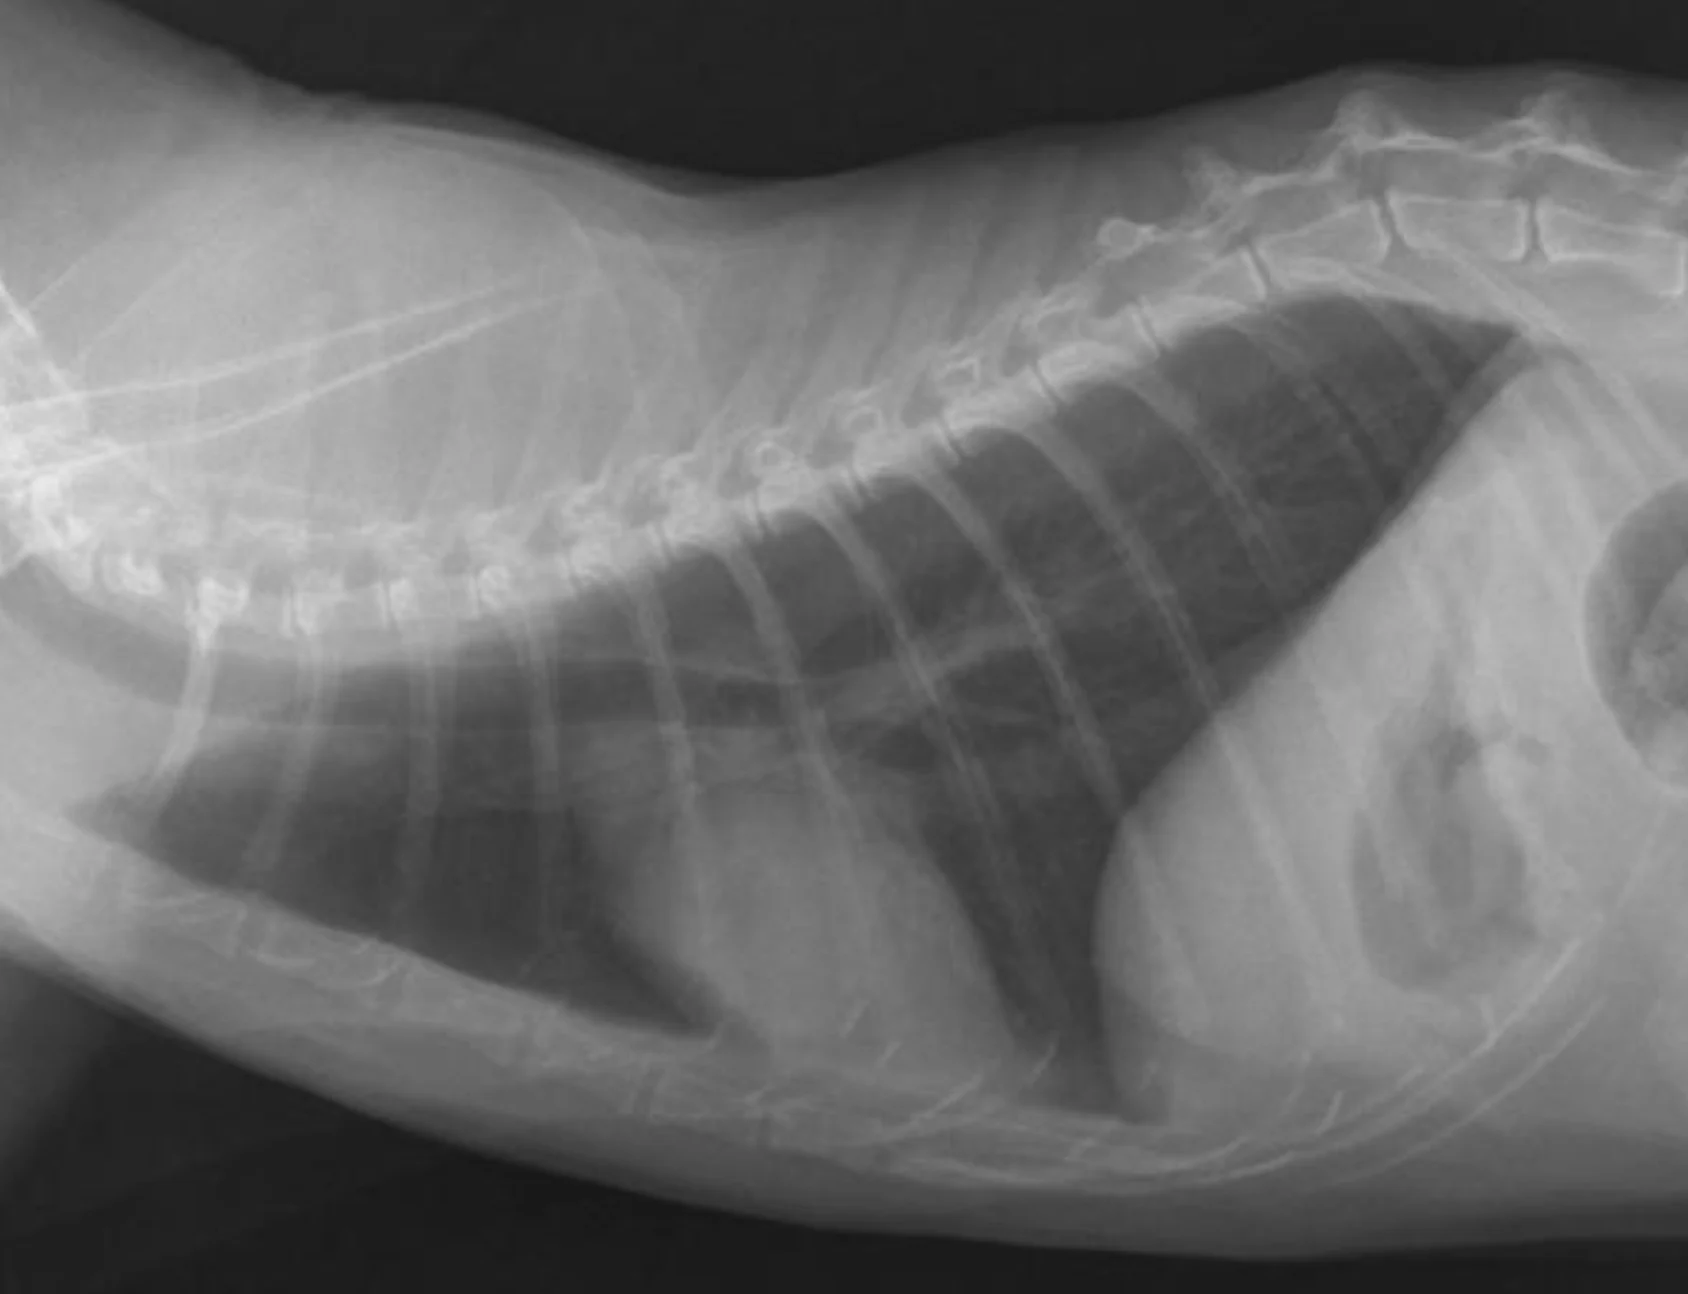

Remember to develop the films with fresh, clean developing solutions-old or exhausted developer will not work for developing technique charts. Examine the films for the setting that gives the best diagnostic quality. In Figure A, the kVp was 56, mA setting was 200, and time was 0.0125 seconds (mAs = 2.5). In this example, the bones are not easily visualized and the film overall is too white (underexposed).

In Figure B, the kVp and mA were left the same and the time was changed to 0.025 seconds (mAs = 5). In this image, the body wall, abdominal organs, and bones can all be readily visualized; this is a proper exposure. In Figure C, the kVp and mA were left the same and the time was changed to 0.05 seconds (mAs = 10). With this higher exposure technique, the ventral body wall cannot be visualized, and the abdomen is too dark (overexposed).